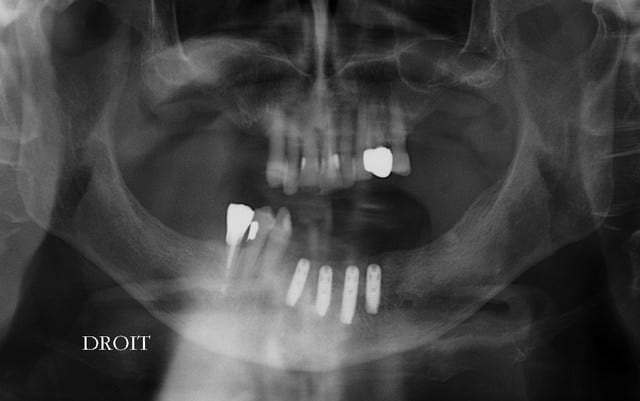

le pano

cicatrisation OK

pas de douleurs

pour le moment RAS

la suite le 25/08